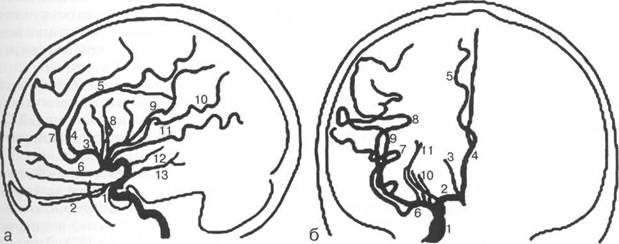

1 - сифон внутренней сонной артерии; 2 - глазничная артерия; 3 - восходящая часть передней мозговой артерии (А2); 4 - дуга передней мозговой артерии вокруг колена мозолистого тела (A3); 5 - перикаллезная артерия; 6 - лобно-полюсная артерия; 7 - каллезо-маргинальная артерия; (Ml);